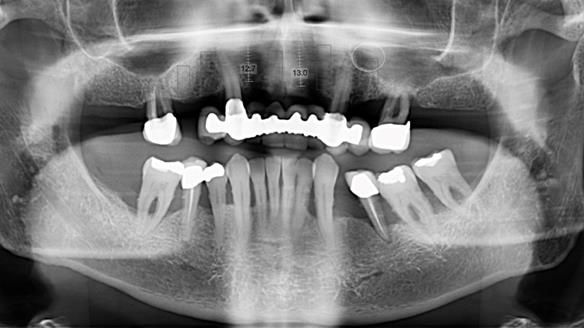

Jeremy’s upper bridge, supported by the canine teeth (13 and 23), was failing both aesthetically and functionally.

- On smiling, the bridge was clearly visible and did not look natural, as the ceramic had been ground back.

- Functionally, the bridge was unstable, due to Periodontitis – Stage IV, Grade C (generalised).

- The upper molars (UR7 and UL7) had also failed and required removal.

- Extract the failed molars and dismantle the bridge.

- Retain the upper canines (13 and 23) after root canal treatment, to support a Mk1 immediate complete denture.

- After 9–12 months, replace the Mk1 with a definitive Mk2 metal-based complete upper denture.

- Periodontal therapy was carried out to help maintain the lower teeth for as long as possible.